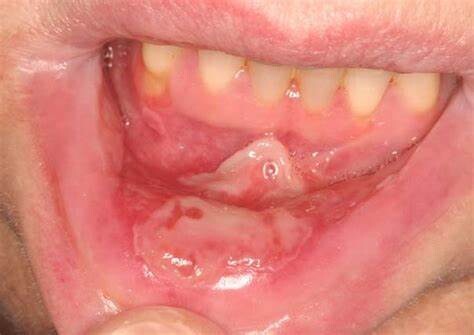

Things to Know about Mucositis

Mucositis, or mouth sores, is a common side effect of chemotherapy, radiation therapy, and bone marrow transplant. The mouth is one of the most sensitive parts of the body and is especially vulnerable to cancer treatment side effects.

Mouth sores can cause pain, poor nutrition (if it hurts too much to eat), and infections. They can affect your quality of life and can lead to limits on your chemotherapy doses. You can help prevent mouth sores and mouth swelling by eating well and having good oral hygiene.

Red, shiny, or swollen mouth and gums

Blood in the mouth

Sores in the mouth or on the gums or tongue

Soreness or pain in the mouth or throat

Difficulty swallowing or talking

Feeling of dryness, mild burning, or pain when eating food

Soft, whitish patches or pus in the mouth or on the tongue

Increased mucus or thicker saliva in the mouth

Mouth sores generally appear 5–10 days after the start of chemotherapy and last anywhere from 1–6 weeks.